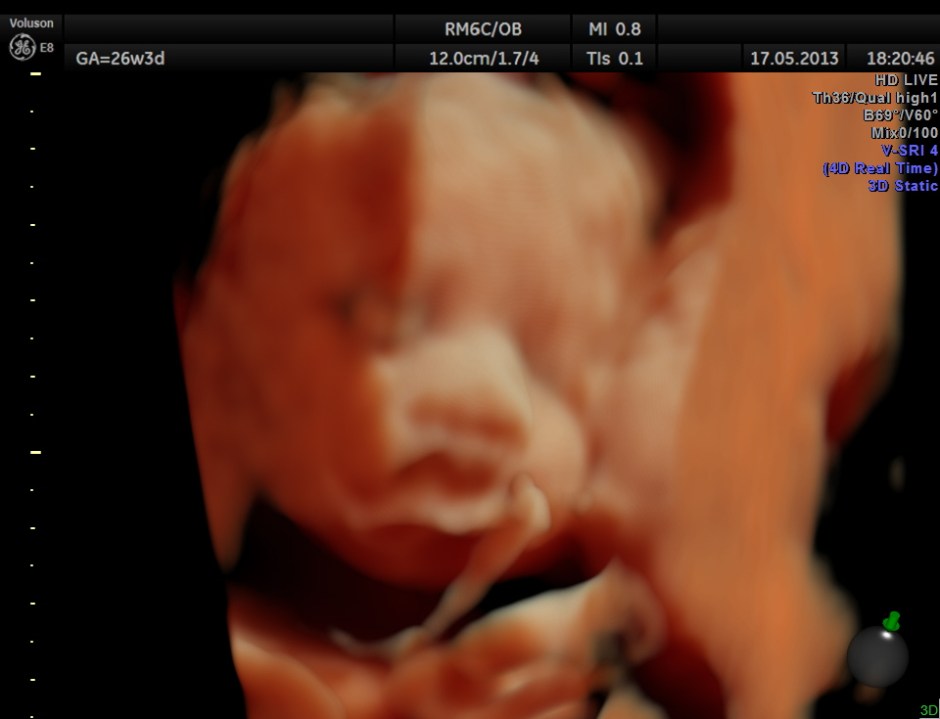

The following are 3 D reconstructed sagittal and coronal images .

The following images show the face and the palate.

This fetus did not show any oro-facial clefts ; heart and spine appeared normal.